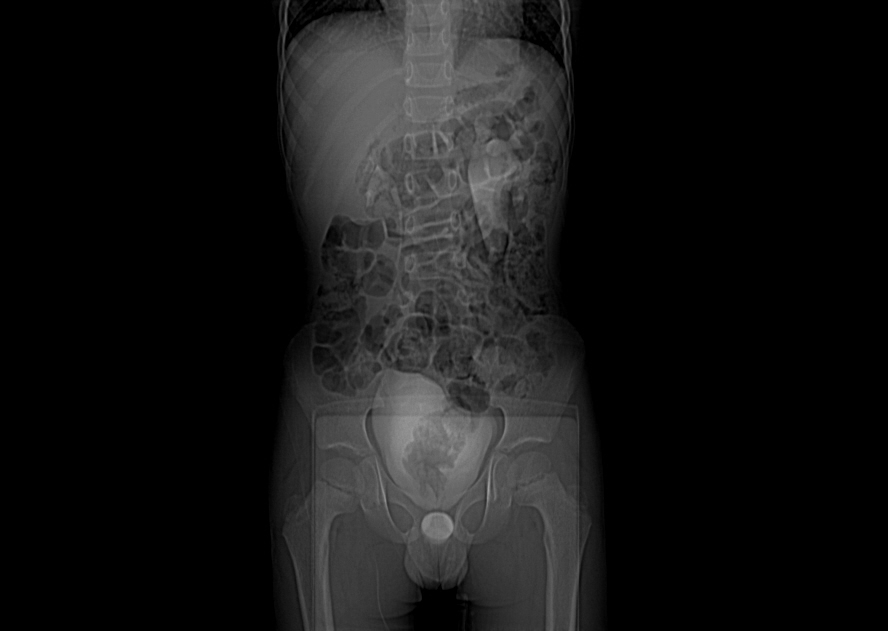

X-Ray's images: